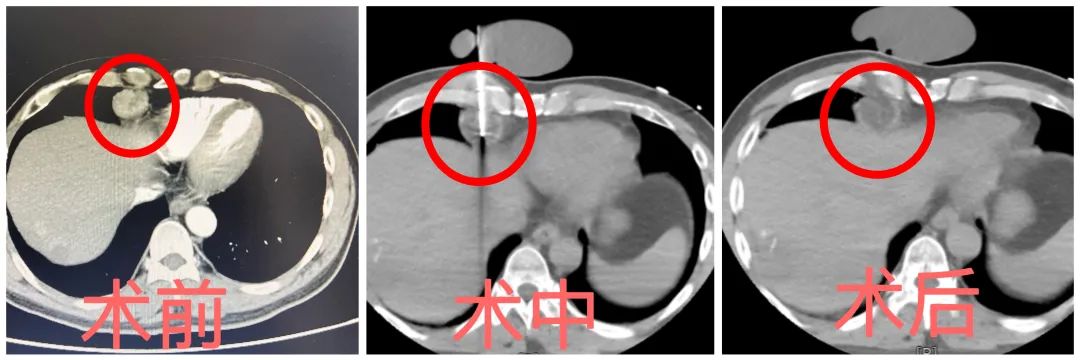

▲图中圈红位置为肿瘤组织

7月7日,张伟主任团队经过详细检查和综合评估,为王叔进行【 心膈角转移瘤氩氦冷冻消融术】 。

手术全程在CT扫描定位下进行,王叔也只需要局部麻醉。

通过氩气, 短时间内产生-140度的超低温度 ,CT显示冰球基本覆盖病灶, 冷冻15分钟,再开通氦气复温(40℃)3分钟 。

术后第3天,复查CT显示,王叔心膈角病变“消失”,次日,王叔顺利出院。